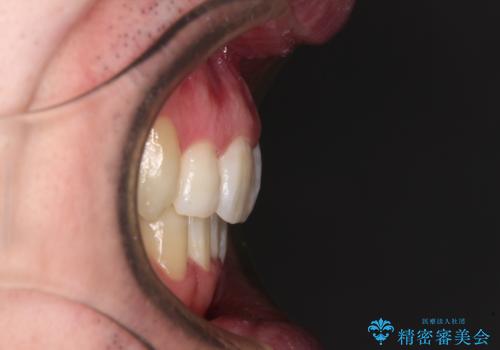

- 前歯のデコボコを気にして来院された患者様です。

叢生の解消とともに、前方に張り出した上顎前歯を引っ込めることを目的とし、上下左右の第一小臼歯4歯を抜歯をしてワイヤー矯正により治療することとしました。